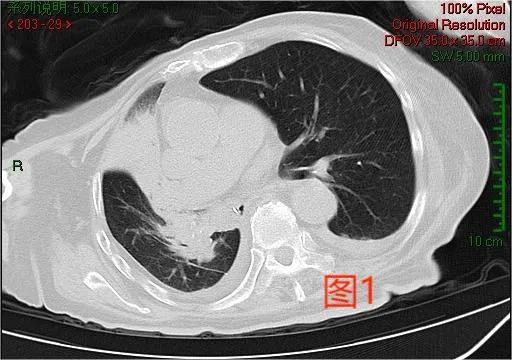

入院时,患者面罩10L吸氧,指末氧在88%波动,新型冠状病毒核酸检测阳性,血常规提示白细胞计数11.6×109/L↑,急诊查胸部CT示:右肺上、中叶实变(如图1)。